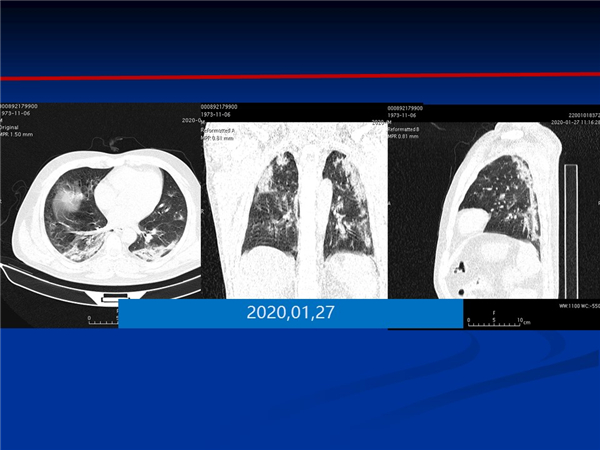

【病例分享】新型冠狀病毒感染肺部CT影像4例(常德市第一人民醫(yī)院)

幻燈片5.jpg